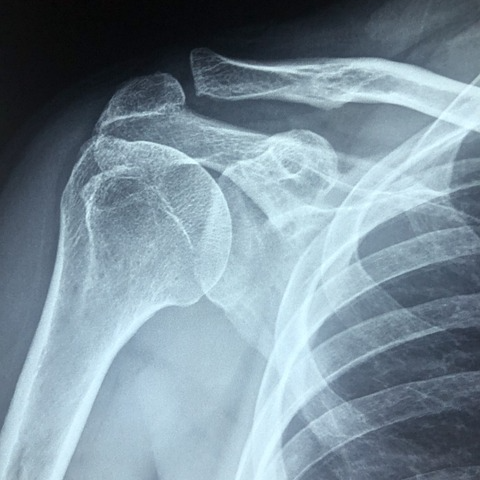

어깨통증은 다양한 원인에 의해 발생하며, 일상생활의 불편함을 초래하는 주요 증상 중 하나입니다.

본 포스팅에서는 어깨통증의 대표적인 원인과 함께 효과적인 치료방법까지 종합적으로 정리하였습니다.

1-5. 어깨 관절염

퇴행성 변화 또는 류마티스성 관절염에 의해 관절 연골이 마모되면서 통증이 유발됩니다. 어깨가 뻣뻣하고, 움직일 때 소리가 나는 경우 의심해볼 수 있습니다.